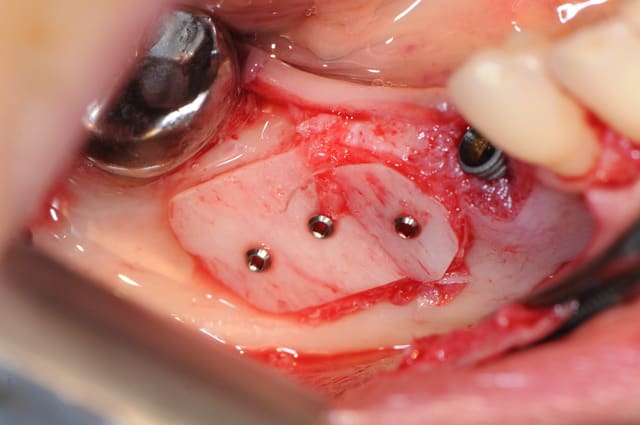

voici la dernière greffe en BioBank faite avec les greffons corticaux que j'ai réalisé il y a 10 jours.

1 situation de départ

2 découpe de la cortical pour aller chercher une racine

3 la racine

4 gros trou ! = apport direct sanguin pour le greffon

5-6 ne pas percer le greffon sur une compresse ! putain, c'est pas possible je suis vraiment têtu ..

7-8 greffon en place avec vis Stoma 1 mm ( Françoise je vais être en rupture de stock!!! et à mon avis je vais pas être le seul)

9 membrane